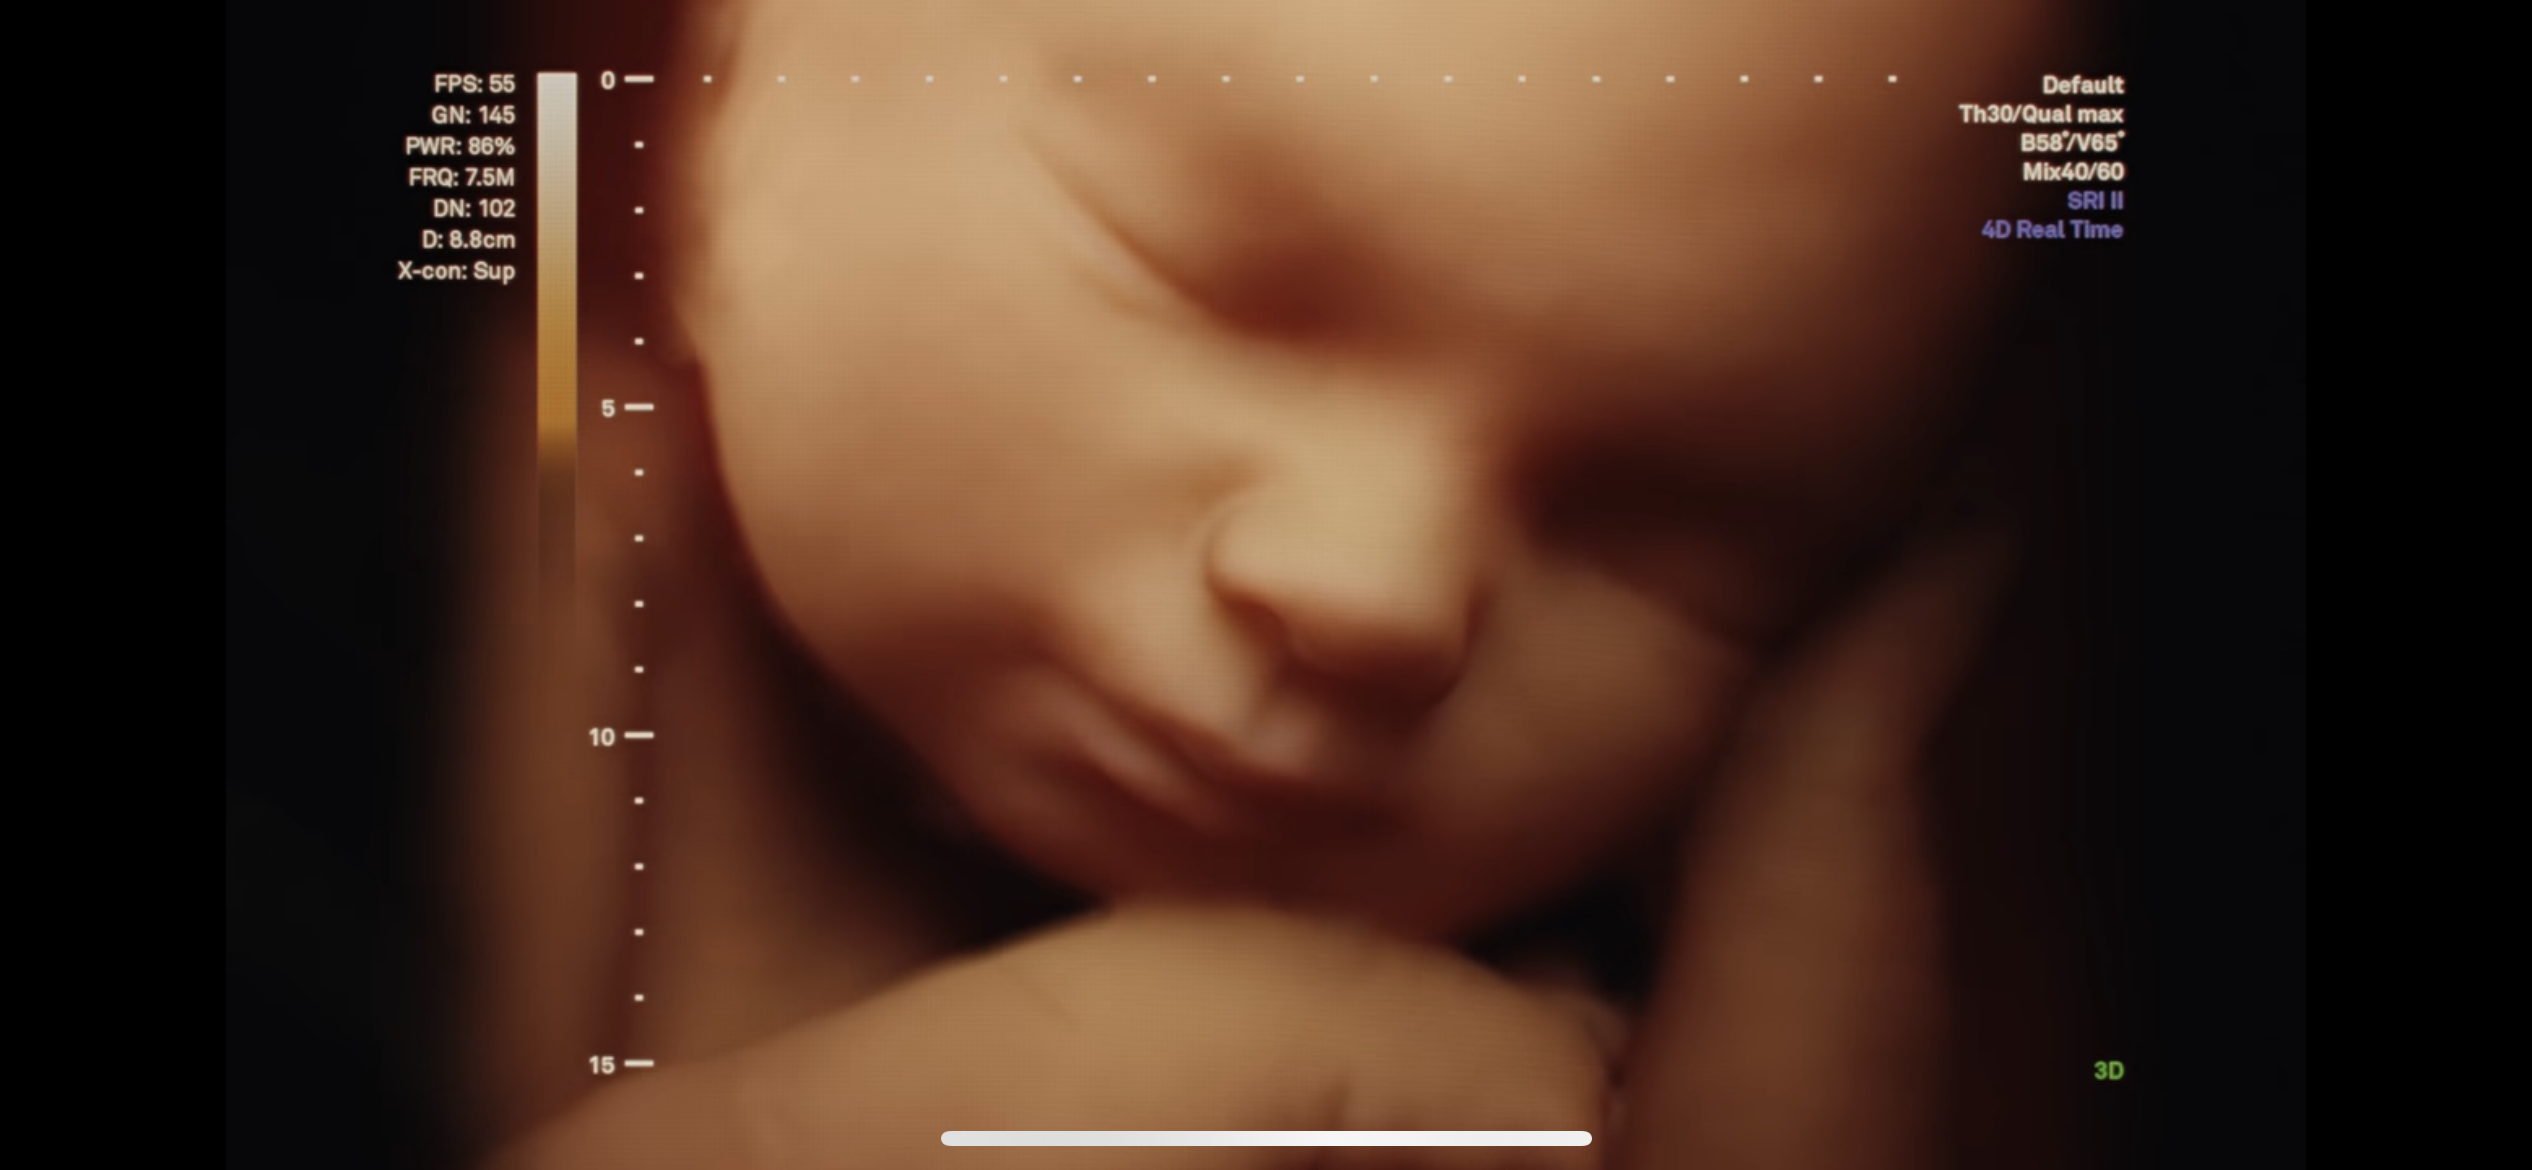

한 부부가 산부인과에서 진료를 받고

여자아이라는 이야기를 듣자 기뻐하는 동시에